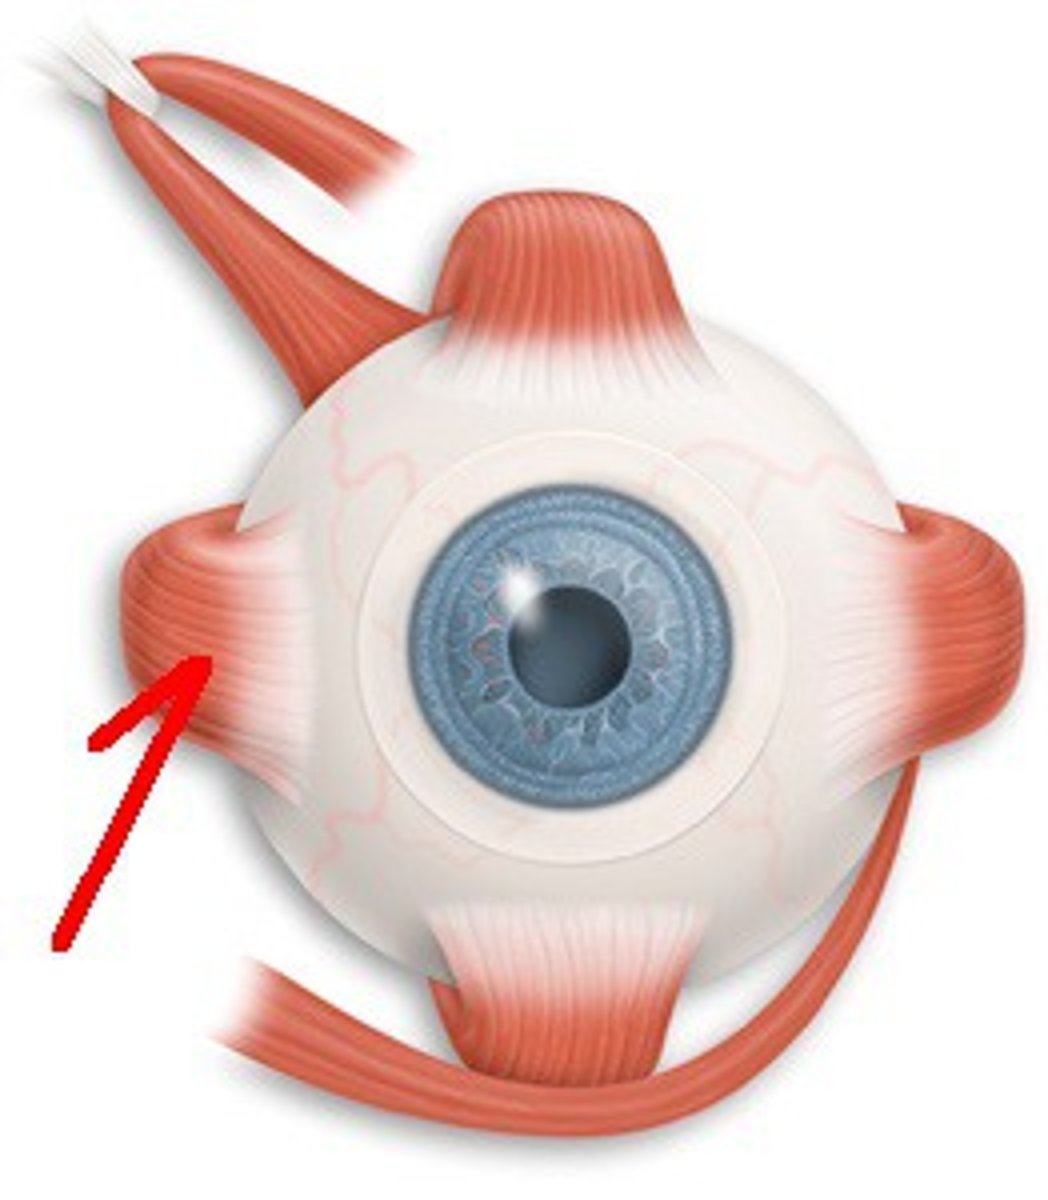

Superior Oblique

A muscle originating in the upper, medial side of the orbit which abducts, depresses and internally rotates the eye

Inferior Oblique

An extraocular muscle, and is attached to the maxillary bone (origin) and the posterior, inferior, lateral surface of the eye

Superior Rectus

One of the extraocular muscles. It elevates, adducts, and helps intort (rotate medially) the eye.

Inferior Rectus

An extraocular muscle. Depresses eye and turns it medially.

Lateral Rectus

A muscle on the lateral side of the eyeball in the orbit

Medial Rectus

The largest of the eye's extraocular movement muscles; adducts the eyeball